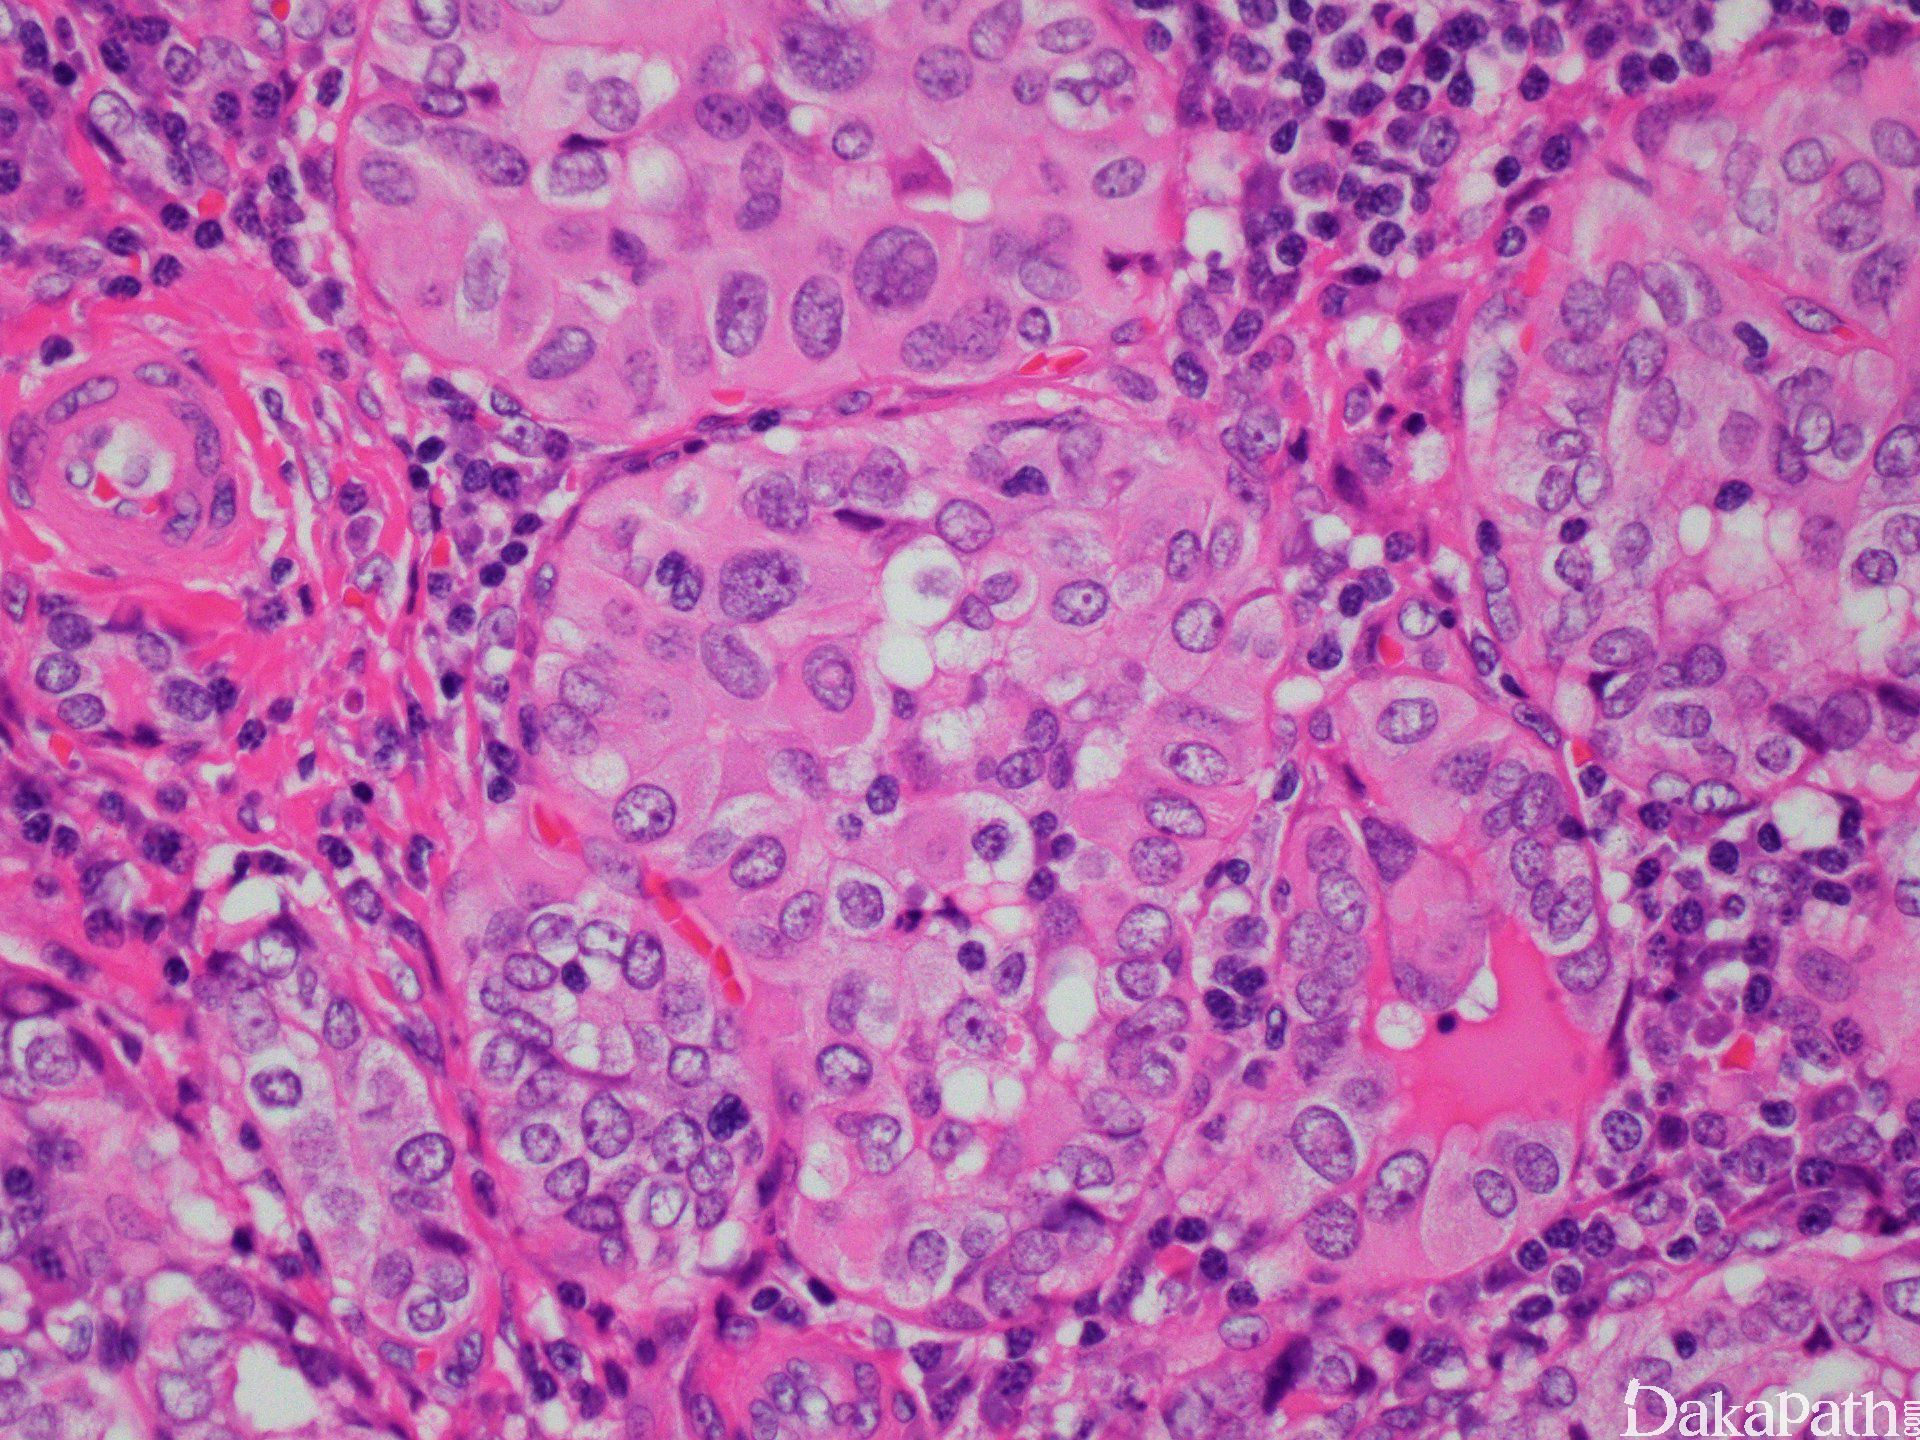

甲状腺乳头状癌(Papillary Thyroid Carcinoma, PTC)约占所有甲状腺癌的80%–85%(NCCN指南,2024),其生物学行为通常较为缓慢,因此在早期阶段通过手术联合放射性碘治疗,大多数患者可以获得长期生存。